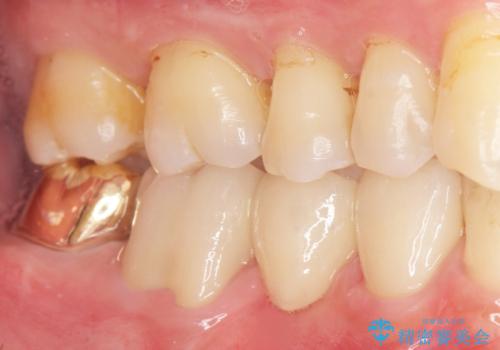

![[ 歯牙破折 ] 違和感のある大臼歯 ブリッジ治療の症例 治療後](https://seimitsushinbi.jp/wp/wp-content/uploads/2021/08/2e4ccba27e1ea02fdacf49749694bbb1-500x350.jpg?v=1629711051)